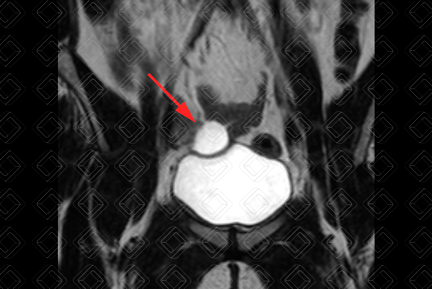

Descrição das figuras 1 e 2: Paciente feminina, 34 anos. Ressonância magnética da pelve ponderada em T2 (planos coronal e axial), mostrando imagem hiperintensa, ovalada, sem septos ou nódulos no seu interior, no anexo direito, medindo 1,2 cm, compatível com cisto simples (seta vermelha).